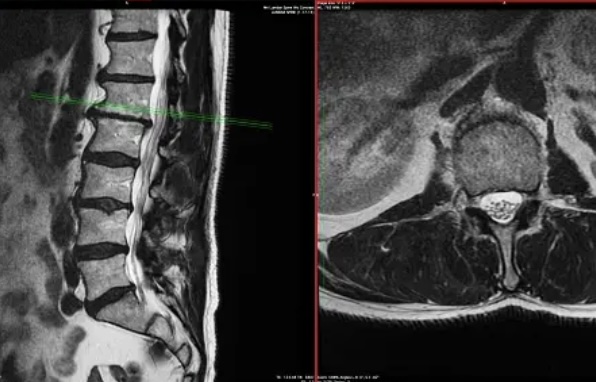

허리디스크 내장증이란 허리 디스크의 변형으로 인해 발생하는 통증을 의미합니다.

디스크의 변형은 나이, 부상, 잘못된 자세, 비만 등의 요인에 의해 발생할 수 있습니다. 이를 관리하기 위해 약물 치료, 물리치료, 수술 등의 다양한 해결방법이 존재합니다. 종합적인 치료 접근법을 통해 허리디스크 내장증 통증을 최소화할 수 있습니다.

허리디스크 내장증의 주요 원인은 디스크의 변형입니다. 디스크는 척추 간의 완충제 역할을 하는 구조로, 변형이 발생하면 주변 조직에 압력을 가하고 통증을 유발할 수 있습니다. 이러한 변형은 여러 가지 요인에 의해 발생할 수 있으며, 가장 일반적인 원인은 나이, 부상, 잘못된 자세, 비만 등이 있습니다. 또한 유전적인 요인도 허리디스크 내장증의 발생 가능성을 높일 수 있습니다.